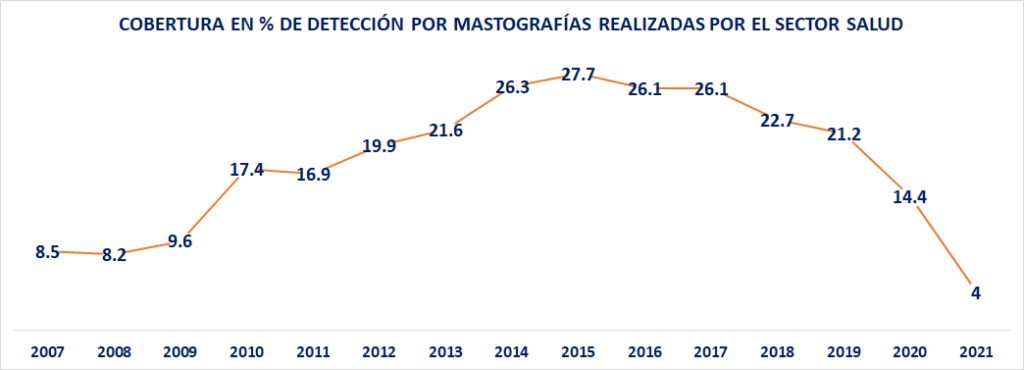

También se desploma la detección oportuna

Debe destacarse que el número de mastografías proyectadas para el año 2021, registra una caída a niveles peores que los registrados en 2007. En ese año, el número fue de 566,103; el indicador llegó a un máximo histórico de 2,436,517 en el año 2012; sin embargo, en 2019 el dato disminuyó a 1,602,464 detecciones; bajó otra vez en 2020 a 1,086,784; mientras que la cifra proyectada en el 2021 es de únicamente 366,077.

Por último, debe subrayarse que el porcentaje de cobertura en detección oportuna por mastografías ha sido siempre muy bajo en el país. Fue de solo 8.5% en 2007; de 8.2% en 2008 y 9.6% en 2009. Creció a 19.9% en el 2012; y llegó a un máximo histórico -claramente insuficiente- en el año 2015, con un 27.7%. Frente a ello, en el 2019 disminuyó a 21.2%; en el 2020 a 14.4% mientras que la proyección 2021 indica un 4%.